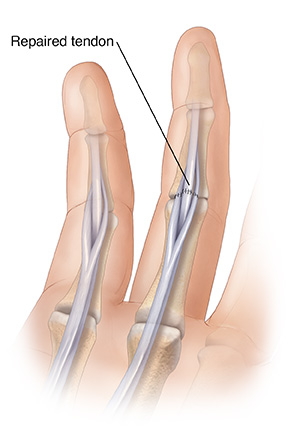

| To rejoin the cut tendon, your healthcare provider stitches the two ends back together. Sometimes nearby tissue also needs to be repaired. |

Then they find the two separated ends and stitch them back together. In some cases, your surgeon may need to graft a new tendon to replace the cut one.